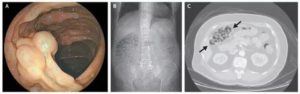

Подтвердить диагноз могут только методы эндоскопии – при них визуально видно газовые пузырьки по ходу кишки.

Могут быть также использованы методы рентгенологической диагностики с контрастом или без него.

Но,чтобы установить точный диагноз, определить пневматоз необходимо пройти ряд диагностических процедур:

- рентген;

- колоноскопию, при которой исследуется полость кишечника на наличие кист;

- эндоскопию, которая позволяет не только установить правильный диагноз и оценить состояние слизистой кишечника, но и взять материал на биопсию, чтобы исключить или подтвердить наличие злокачественных образований.